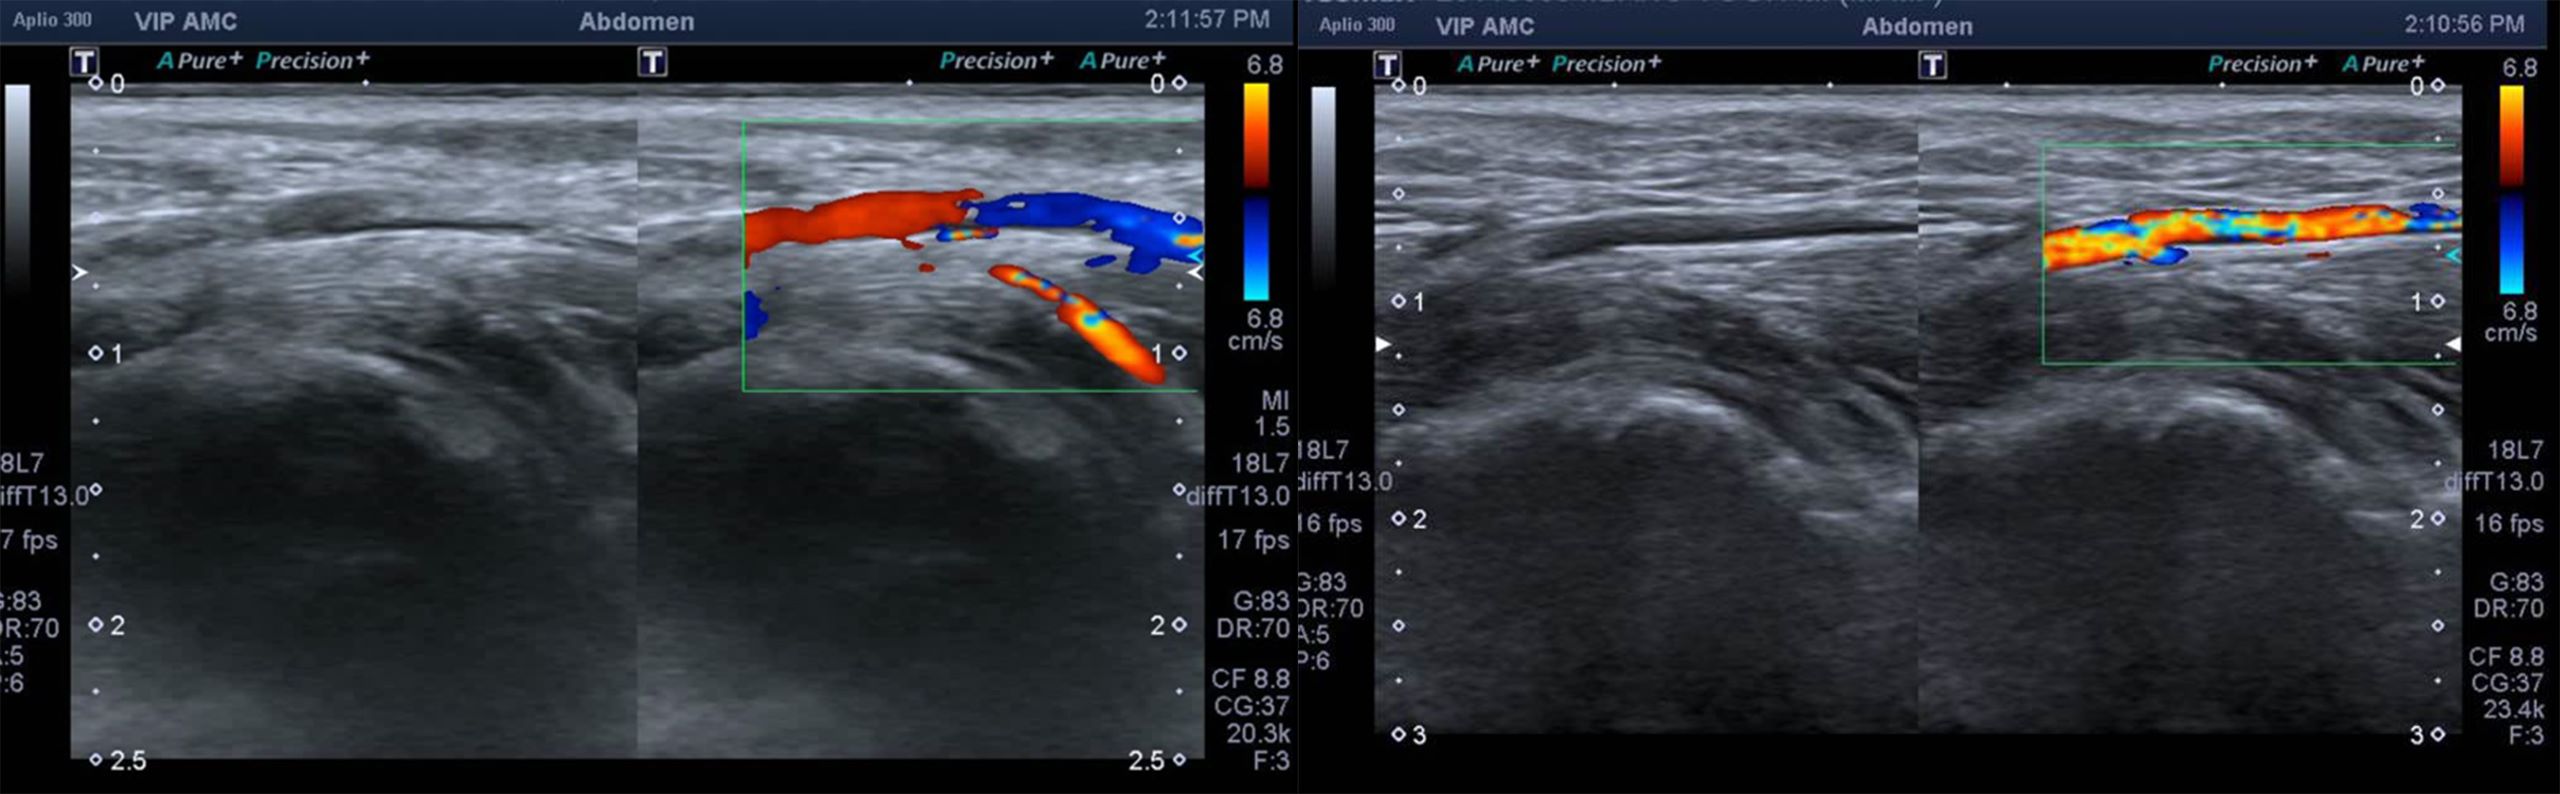

비비의 복부 초음파 결과, 도플러 검사 상 대동맥 내 색상이 관찰되지 않으며 혈전에 의한 혈류 흐름에 문제가 있는 것을 발견하였습니다. 복강 후방 대동맥의 분지 부분에서 혈전 덩어리가 관찰되었습니다. 혈전 덩어리로 인해 혈류가 잘 흐르지 않는 것을 확인할 수 있었습니다.

비비의 치료 후 복부 초음파 검사 혈전의 소실이 확인된 것을 볼 수 있었으며 Lactate 농도 검사상 수치의 감소가 확인된 것을 알 수 있었으며 뒷다리의 냉감 개선 및 추후 소실 확인이 되었고 보행이 개선되었음을 알 수 있었습니다. 향후 정기적인 심장 초음파 검사 및 proBNP와 같은 내과적 검사 재검 이 추천되었습니다.